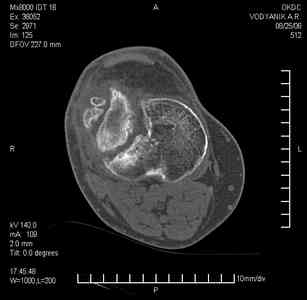

Уважаемые коллеги,В ортопедическое отделение обратился пациент: мужчина 47 лет, который в течение 4-х лет дваждыполучил травму костей, образующих правый коленный сустав. В 2002 v внутрисуставной оскольчатыйперелом проксимального метаэпифиза правой большеберцовой кости; в 2005 v внутрисуставнойоскольчатый перелом дистального метаэпифиза правой бедренной кости. В обоих случаях в разных лечебных учреждениях проводилось оперативное лечение переломов.При осмотре в отделении на основании результатов клинического осмотра и данных визуальныхметодов обследования поставлен диагноз:тугой ложный сустав дистальной трети правой бедренной кости, состояние после накостногоостеосинтеза перелома типа 33-В2.2 ; несросшийся перелом надколенника; неправильно сросшийсяперелом латерального мыщелка правой большеберцовой кости, состояние после металлоостеосинтезаперелома 41-В2.2; сочетанная осевая деформация правой ноги: варусная деформация правого бедра,вальгусная деформация правой голени; посттравматический артроз коленного сустава 4 ст по Kellgren-Lowrence; выраженное нарушение функции ходьбы и опоры. Внешний вид ноги больного, данные рентгенографического обследования и избирательно выделенные компьютерные томограммы приведены в приложении. В именах КТ использовано кодирование уровня по АО, т.е. _41, например, означает проксимальную треть голени.В отделении намечен v очень предварительно v следующий план лечения: 1. Иметь ввиду перспективу тотального эндопротезирования коленного сустава. 2. С учетом п.1 при проведении действий, направленных на устранение ложного сустава бедренной кости не использовать материалы, не подвергающиеся трансформации. 3. В ходе операции, направленной на устранение ложного сустава: А. удалить все металлоконструкции; Б. ревизовать зону пролежня под пластиной на бедре, при наличии признаков достаточной жизнеспособности кости выполнить остеопериостальную декортикацию, дрилинг ложа пластины; В. Удалить рубцовую ткань по плоскости ложного сустава, и в пространстве между костными форагментами, насечь обращенные друг к другу поверхности. Ввести штифт с блокированием (например Stryker с учетом особенностей расположения дистальных блокирующих винтов у этойконструкции). Осуществить остеосинтез с учтанением варусной деформации бедренной кости. Пространство в зоне ложного сустава и пустоты в метафизе бедренной кости заполнить резорбирующимся цементом на основе гидроксиапатита кальция. Для дистальной фиксации использовать винты с переменным шагом резьбы. Вариант:, винты вводить после заполнения метафиза цементом. Дополнительные виды создания межфрагментарной компрессии во встречно-боковом направлении обсуждаются. Г. Быть готовым к кровопотере. Д. Учесть высокий риск инфекции, тромбоэмболических осложнений. Е. Вопрос о внешней иммобилизации решить по результатам оценки стабильности остеосинтеза. Вариант - одноосевой стержневой аппарат для шунтирования гвоздя с модулем на голени и дистракцией коленного сустава в течение 3-5 недель. Просим вашей критики намеченного плана и конструктивных предложений. С уважением к сообществу, Ординатор В.С. Саплин

Движения приличные, есть за что бороться. Такая ротация голени кнаружи, если она действительно есть (для уточнения можно сделать КТ на уровне обоих метафизов и бедреных, и берцовых ксотей, не меняя положение ног во время съемки), большого значения не имеет. А уж на фоне всего остального тут - вообще говорить не о чем.